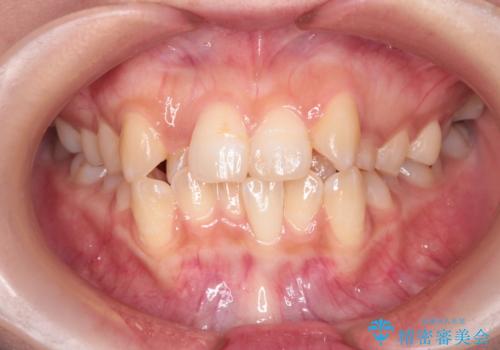

[ マウスピース矯正] 前歯のがたつき 出っ歯に見える歯をきれいに

![[ マウスピース矯正] 前歯のがたつき 出っ歯に見える歯をきれいに の症例 治療後](https://seimitsushinbi.jp/wp/wp-content/uploads/2025/04/a5c1eab0aff12598c7b5c9fb710c2648-500x350.jpg?v=1744960670)